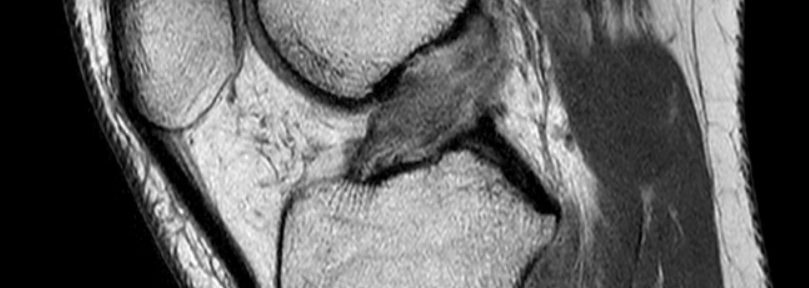

治療前MRI:2022年12月22日

三位獨立放射科醫師根據伊原分類對MRI影像進行評估。

- 伊原分類: 兩位醫師評為類型III(韌帶殘端移位),一位評為類型II(韌帶殘端未移位)